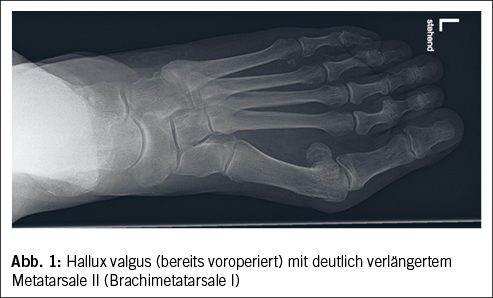

Bei den mechanischen Ursachen besteht meist eine relative Überlänge des 2. Metatarsales relativ zum ersten Metatarsale oder eine Instabilität der Metatarsophalangealgelenke (Abb. 1). Diese führen zu einer unphysiologischen Belastung des Vorfusses. Die Fehl- oder Überlastung wird zusätzlich noch begünstigt durch das regelmässigen Tragen von ungedämpften Schuhen, hohen Absätzen und das Gehen auf hartem Boden. Das Gewebe reagiert darauf mit funktionellen Einschränkungen und strukturellen Veränderungen (1).

Beim Hallux valgus führt die Fehlstellung des 1. Metatarsophalangeal (MTP)-Gelenks zu einer vermehrten Belastung der benachbarten MTP-Gelenke (2), was sich Transfermetatarsalgie nennt und sich unterhalb vom 2. und 3. (Abb. 1) MTP-Gelenk bemerkbar macht. Der Hallux valgus tritt häufiger bei Frauen auf. Frauen über 65 Jahre leiden mit einer Wahrscheinlichkeit von 35% an einer Hallux-valgus-Fehlstellung (3).

Ein sehr kurzes erstes Metatarsale, sog. Brachimetatarsale I, kann die Überlastung vom MTP-II- und -III-Gelenk zusätzlich verstärken (Abb. 1). Dieses führt ebenfalls zu einer relativen Überlänge der lateralen Strahlen im Verhältnis zum Metatarsale I.